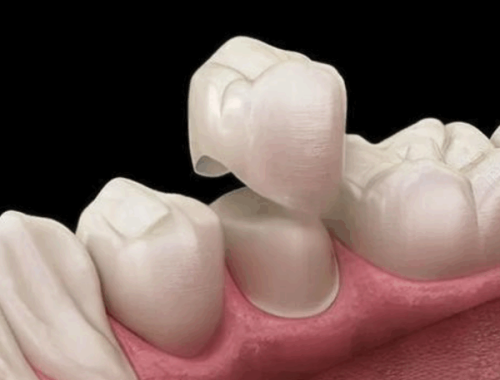

常规正畸矫正:适合恒牙期的牙性地包天患者,常用的矫治方式包括金属托槽矫正和隐形矫正,比如时代天使、隐适美等隐形正畸品牌,隐形矫正的费用大概在30000~60000元之间,金属托槽矫正的费用相对更低一些。

正畸正颌联合治疗:针对重度的骨性地包天患者,需要由正畸医生和正颌外科医生联合完成治疗,国内有不少专精的医疗团队可以开展这类高难度手术,可以精细改善复杂的骨性错颌问题,全方面修复咬合功能和面部美观。

比如曾有12岁的骨性地包天患者,采用「FR-Ⅲ型肌功能矫治器+时代天使隐形矫正」的联合方案,仅用半年就完成了矫正,患者的咬合关系修复正常,面型也从原本的凹面型转变为直面型,总费用约28000~35000元。